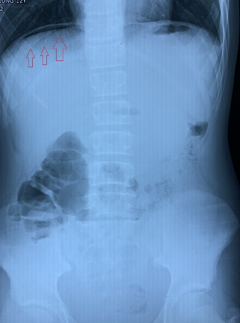

Liềm hơi dưới vòm hoành rất có giá trị trong chẩn đoán thủng

tạng rỗng

không điều trị, BN nhập viện trong tình trạng đau bụng dữ dội, Xquang có hình ảnh

liền hơi, được chẩn đoán Viêm phúc mạc do thủng tạng rỗng. BN đã được ê-kíp trực